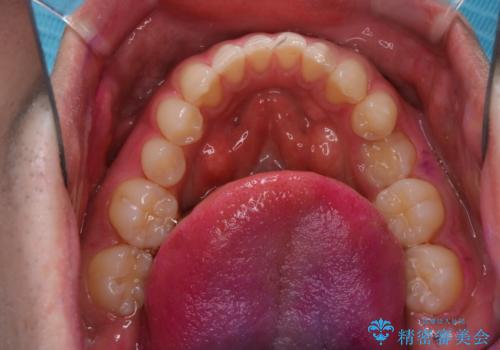

親知らずを抜いて1週間後にPMTC 歯のクリーニング

- 親知らずの抜歯後の約1週間後に抜糸(縫った部分の糸とり)で来院されました。その際、抜歯後は傷口が怖くて歯磨きが上手くできず、汚れや口臭が気になるためクリーニングも希望されました。

抜歯後は多少出血したり、違和感や痛みを感じたりすることがあります。そのため親知らずを抜いたり、外科的な処置をするといつも通りの歯磨きがしづらくなります。また、傷口の周りが心配で、歯ブラシをするのが怖くなるものです。抜歯後落ち着いたら、歯科医院にて専門の機械を使用しクリーニングをすることがおすすめです。抜歯前や後にPMTCを行うことで、お口の中の健康維持につながり、その後の感染・腫れ・口臭予防などになります。

親知らず抜歯後正常に治癒が進んでいれば1週間後から可能です。